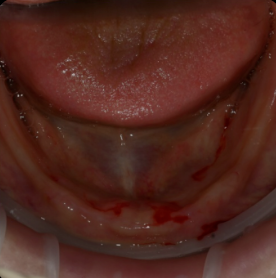

그렇다면

티타늄바가 필요한 경우는?

이갈이가 심한 경우

스플린트를 꼭 껴야하는 경우

뼈가 없어 허공에

뜬 부분이 매우 긴 경우

높이 22미리 이상으로

보철이 너무 큰 경우